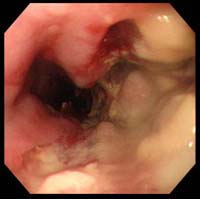

±â°üÁö ³»½Ã°æ °Ë»ç

Æó¾ÏÀ» È®ÁøÇϴµ¥

ÇʼöÀûÀÎ °Ë»ç·Î À§¾Ï Áø´Ü½Ã ÇÊ¿äÇÑ À§

³»½Ã°æÃ³·³ ±â°üÁö ³»ºÎ¸¦ °üÂûÇϸé¼

¾Ï Á¾±«°¡ ¹ß°ßµÇ¸é Á¶Á÷ °Ë»ç¸¦ ½ÃÇà